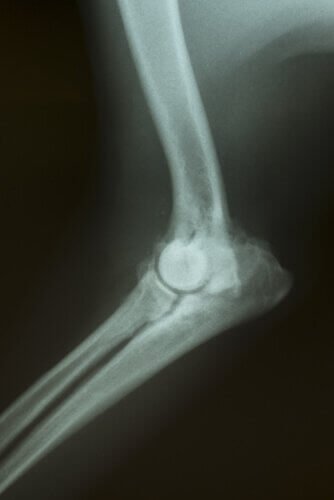

In base ai sintomi, potrebbero essere necessari alcuni esami per determinare la causa del problema. Potranno essere fatti: analisi del sangue, radiografie, ultrasuoni, tomografie, ecc.

- Infine, per quanto riguarda le ossa e il midollo osseo, è possibile realizzare la biopsia con l’aiuto di aghi speciali.